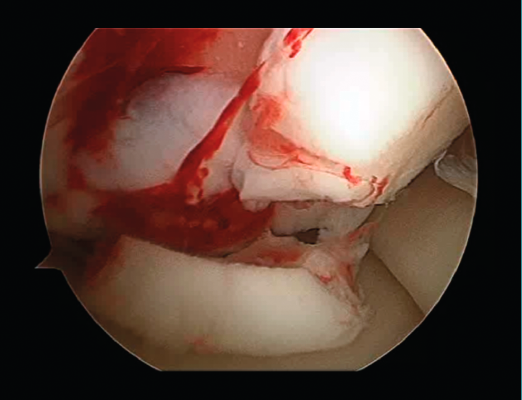

First surgery involves arthroscopy of the damaged joint. It assesses the chondral lesion to be treated and confirms whether it is amenable to the chondrocyte implantation technique (Figures 1 and 2). Other procedures are also carried out if needed, such as for example reconstruction of the anterior cruciate ligament, partial meniscectomies, meniscus implantation, patellar realignments, osteotomies, etc. Lastly, the cartilage sample is taken from a non-weight bearing zone (intercondylar zone or internal femoral condyle at its upper margin). The sample is extracted with biopsy forceps or, alternatively, using discectomy forceps. Between 3-4 rice grain-sized fragments of healthy cartilage are harvested (Figure 3). The biopsy material is placed in a sterile receptacle containing a culture medium (DMEN) (Figure 4). The material is kept at room temperature and is shipped to the laboratory as quickly as possible. A form should be completed (Figure 5), stating the joint, the location of the lesion and the size of the defect. Once in the laboratory, the sample is processed and cultured. After 4-6 weeks (depending on the case), the culture is ready for implantation.

Figure 1. Arthroscopic view of an Outerbridge grade IV acute chondral lesion of the internal femoral condyle.